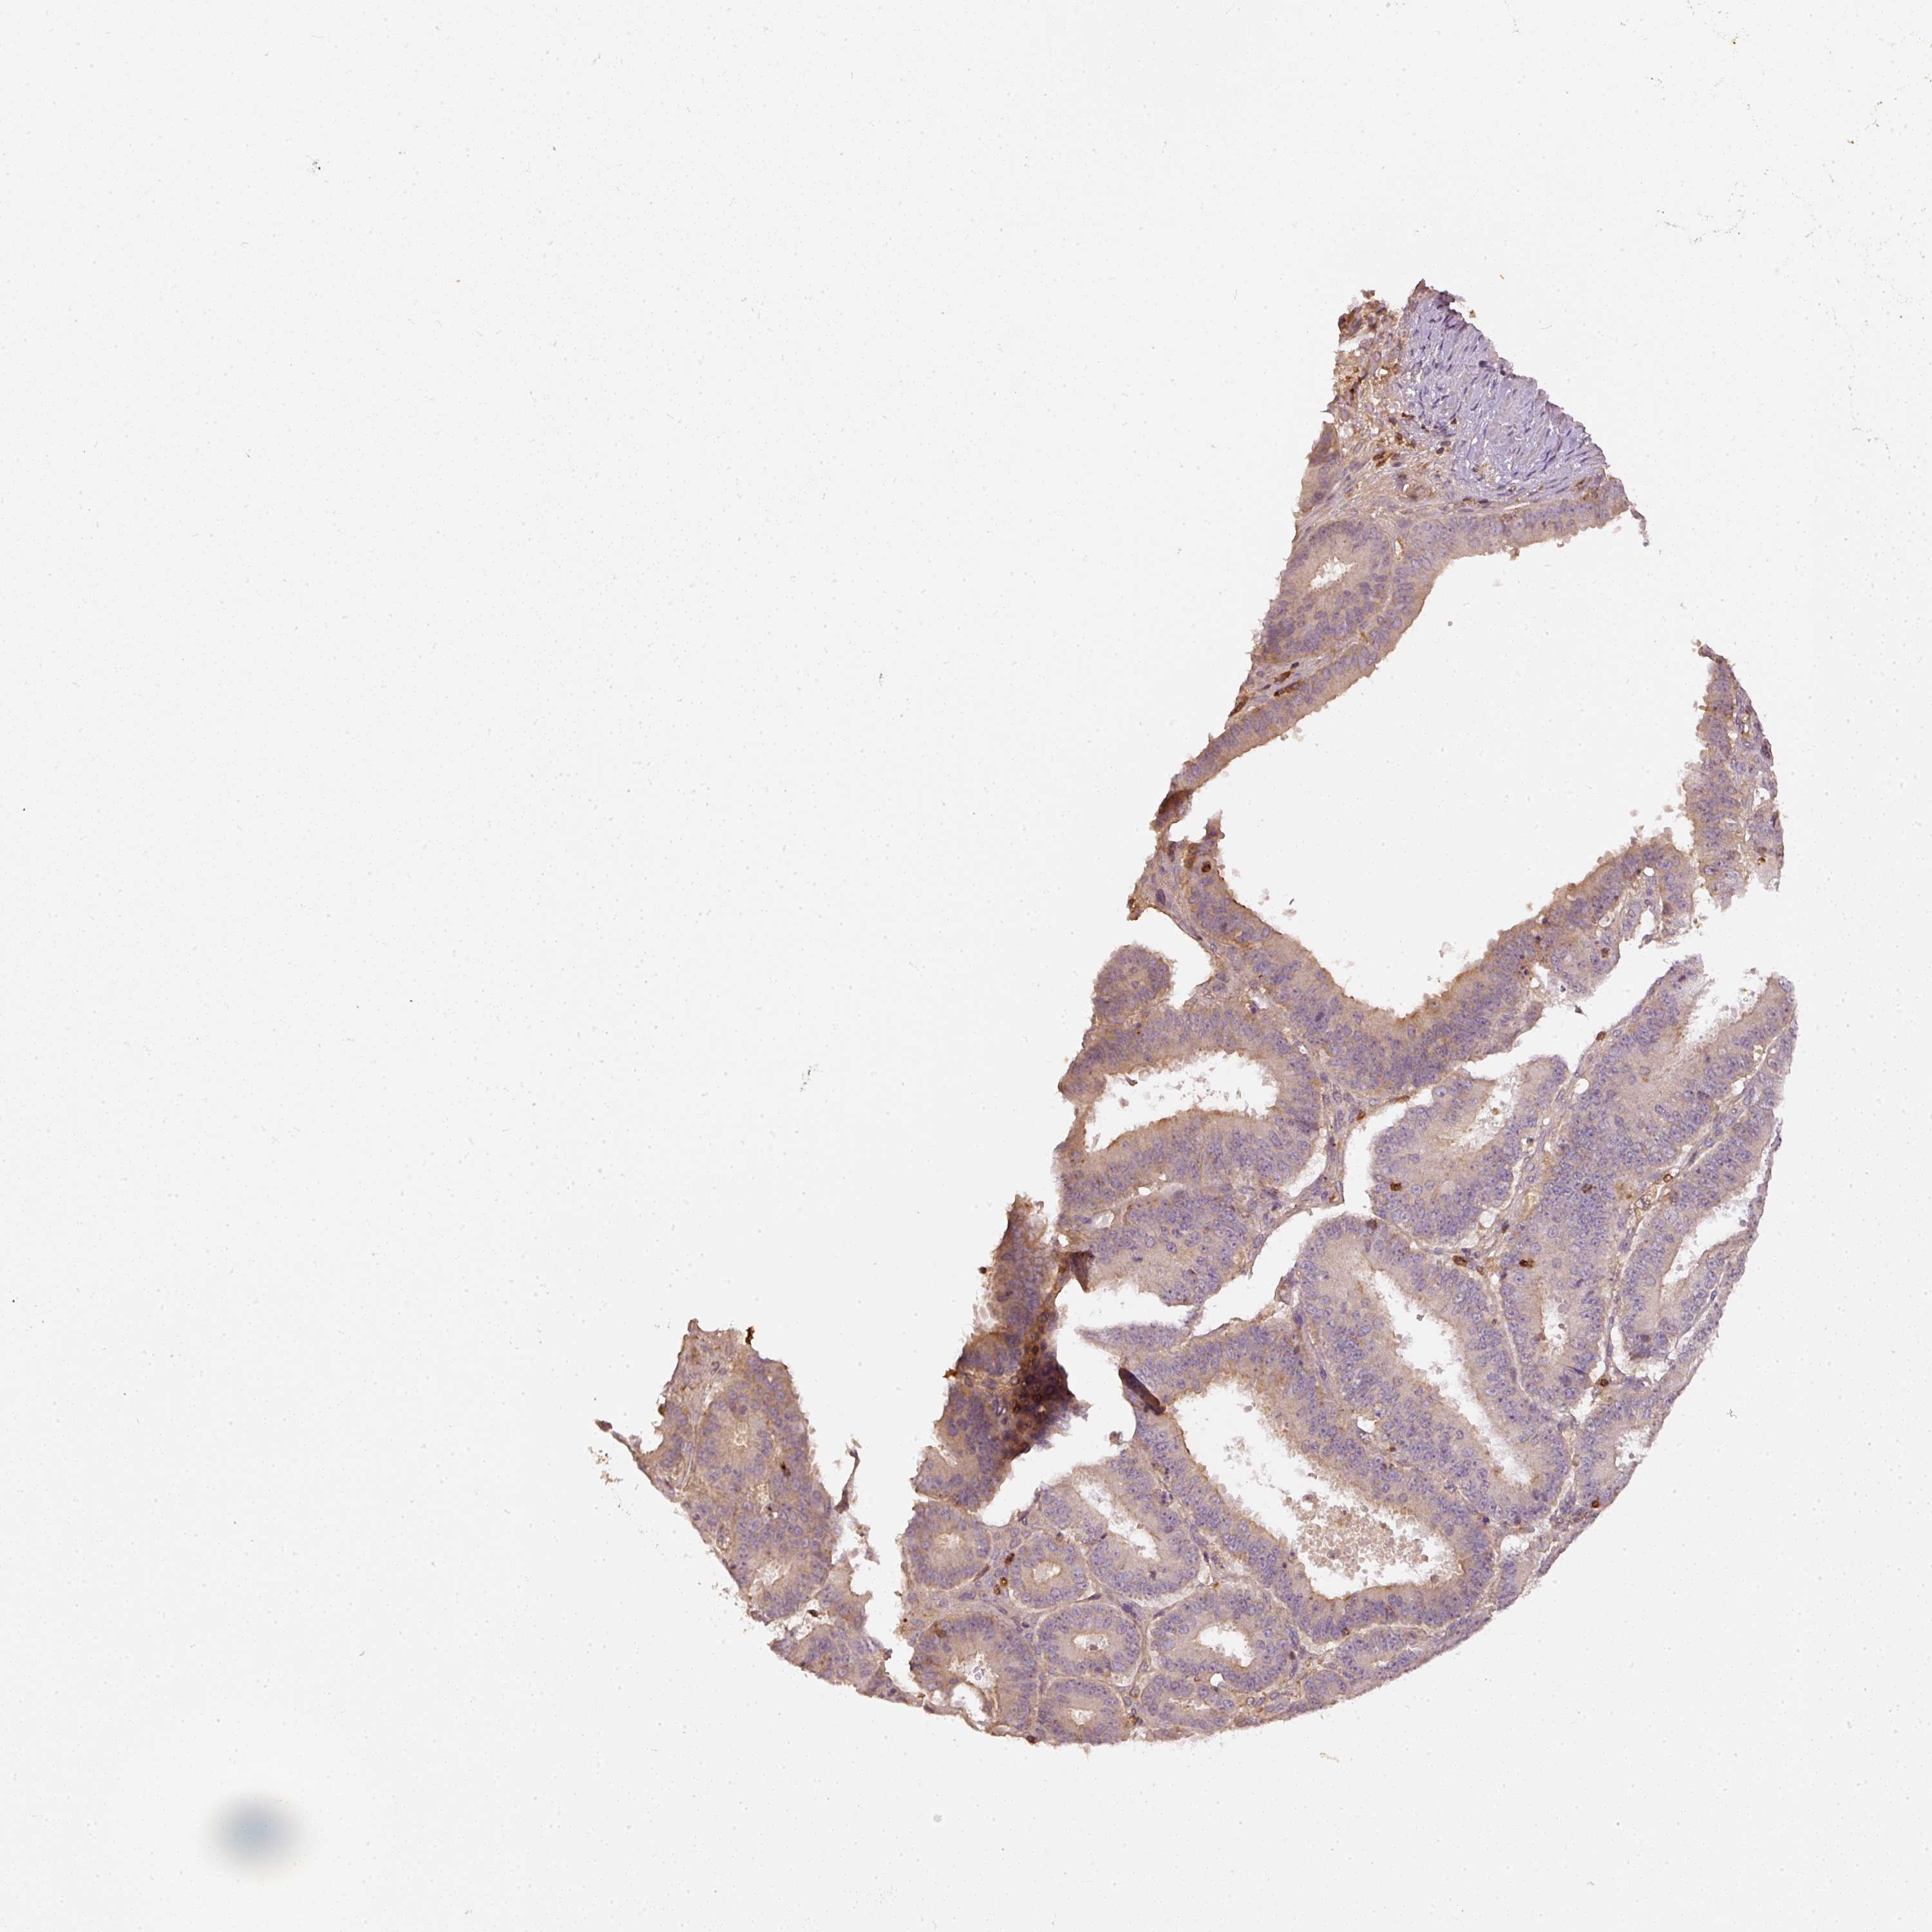

OVARIAN CANCER - Protein expressioni

A mouse-over function shows sample information and annotation data. Click on an image to view it in a full screen mode. Samples can be filtered based on level of antibody staining by selecting one or several of the following categories: high, medium, low and not detected. The assay and annotation is described here.

Note that samples used for immunohistochemistry by the Human Protein Atlas do not correspond to samples in the TCGA dataset.

Antibody stainingi

Antibody staining in the annotated cell types in the current human tissue is reported as not detected, low, medium, or high, based on conventional immunohistochemistry profiling in selected tissues. This score is based on the combination of the staining intensity and fraction of stained cells.

Each image is clickable and will lead to virtual microscopy that enables deeper exploration of all samples and also displays staining intensity scores, fraction scores and subcellular localization as well as patient and tissue information for each sample.

Antibody HPA019536

Carcinoma, endometroid